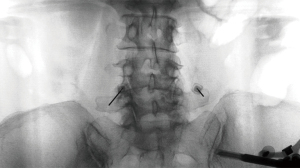

A 22-gauge spinal needle is advanced in-plane towards the identified target, ensuring accurate positioning relative to the bone structure. Post-placement, an AP (anterior-posterior) radiograph is captured to confirm the proper placement of the needle (Figure 5). This step is crucial to ensure the needle is correctly situated within the plane before injection (Figure 6).